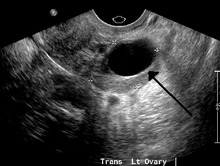

| A simple ovarian cyst of most likely follicular origin | |

- Transvaginal ultrasonography showing a 67 x 40 mm endometrioma, with a somewhat grainy content.

Ovarian cysts are usually diagnosed by ultrasound, CT scan, or MRI, and correlated with clinical presentation and endocrinologic tests as appropriate.[10]

Ultrasound

Follow-up imaging in women of reproductive age for incidentally discovered simple cysts on ultrasound is not needed until 5 cm, as these are usually normal ovarian follicles. Simple cysts 5 to 7 cm in premenopausal females should be followed yearly. Simple cysts larger than 7 cm require further imaging with MRI or surgical assessment. Because they are large, they cannot be reliably assessed by ultrasound alone; it can be difficult to see posterior wall soft tissue nodularity or thickened septation due to limited ultrasound beam penetrance at this size and depth. For the corpus luteum, a dominant ovulating follicle that typically appears as a cyst with circumferentially thickened walls and crenulated inner margins, follow up is not needed if the cyst is less than 3 cm in diameter. In postmenopausal patients, any simple cyst greater than 1 cm but less than 7 cm needs yearly follow-up, while those greater than 7 cm need MRI or surgical evaluation, similar to reproductive age females.[11]